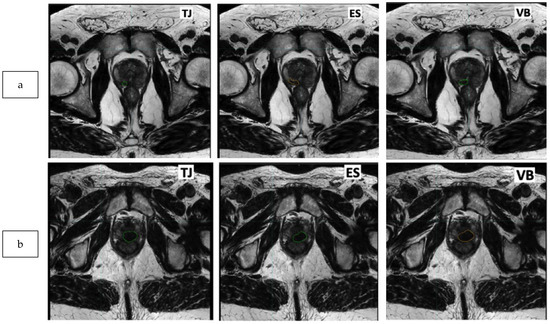

2.3. Delineation of the Dominant Index Lesion (DIL)